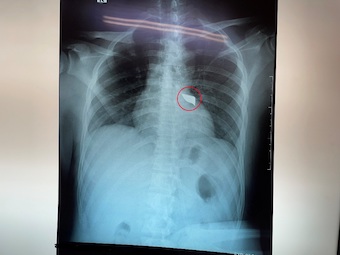

Nam thanh niên 30 tuổi bị dao đâm vào cột sống. Khiến phải mang cả mũi dao cắm sâu vào lưng đến bệnh viện cấp cứu. Các bác sĩ đã phải nhanh chóng lấy mũi dao ra khỏi người bệnh nhân.

Chiều 8/4, tin từ bệnh viện Đa khoa Trung ương Cần Thơ, các bác sĩ khoa Ngoại Thần kinh đã phẫu thuật cấp cứu lấy thành công mũi dao đâm vào cột sống nam bệnh nhân T.H.T.H, 30 tuổi, ngụ tỉnh Sóc Trăng.

Tình trạng lúc nhập viện, bệnh nhân H. tỉnh, niêm hồng, than đau lưng, khó thở nhẹ với vết thương lưng thành ngực sau cạnh trái cột sống đoạn ngực 4-5 rỉ máu, còn dị vật, không tê yếu chi, dấu hiệu sinh tồn ổn định.

Các bác sĩ khoa Cấp cứu nhanh chóng xử trí cấp cứu và thực hiện các xét nghiệm, siêu âm, chụp Xquang tim phổi thẳng, chụp cắt lớp vi tính lồng ngực… Việc hội chẩn phẫu thuật được ê-kíp bác sĩ khẩn tiến hành và thống nhất phương án xử lý thám sát vết thương và lấy dị vật cấp cứu.

Sau 90 phút phẫu thuật, ê-kíp phẫu thuật gồm: Bs.CK2 Trần Văn Minh – Phó Trưởng, khoa Ngoại Thần kinh, Bs. Nguyễn Châu Thanh, Bs.CK1 Nguyễn Văn Vĩnh – Khoa Phẫu thuật – Gây mê hồi sức đã lấy thành công mũi dao dài 5x2cm ra ngoài.